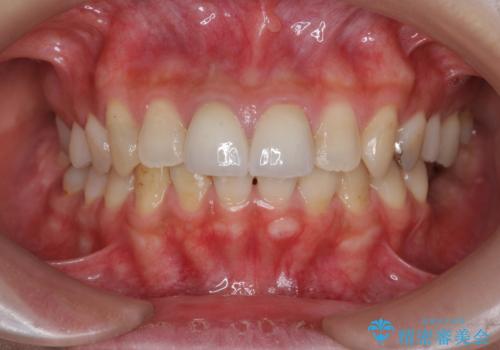

- 前歯の見た目、変色の改善を希望され来院されました。

ジルコニアクラウンによる審美性の改善を計画します。

- 24万円(仮歯・ファイバーコア・ジルコニアクラウン)費用は治療当時の料金となります

神経の治療をした歯について

神経をとる治療を行った歯は、時間が経過すると術前のように変色し見た目を大きく損ないます。

このような場合金属を使わないジルコニアクラウンを用いた治療を行うことで天然の歯のように審美性を改善することが可能になります。